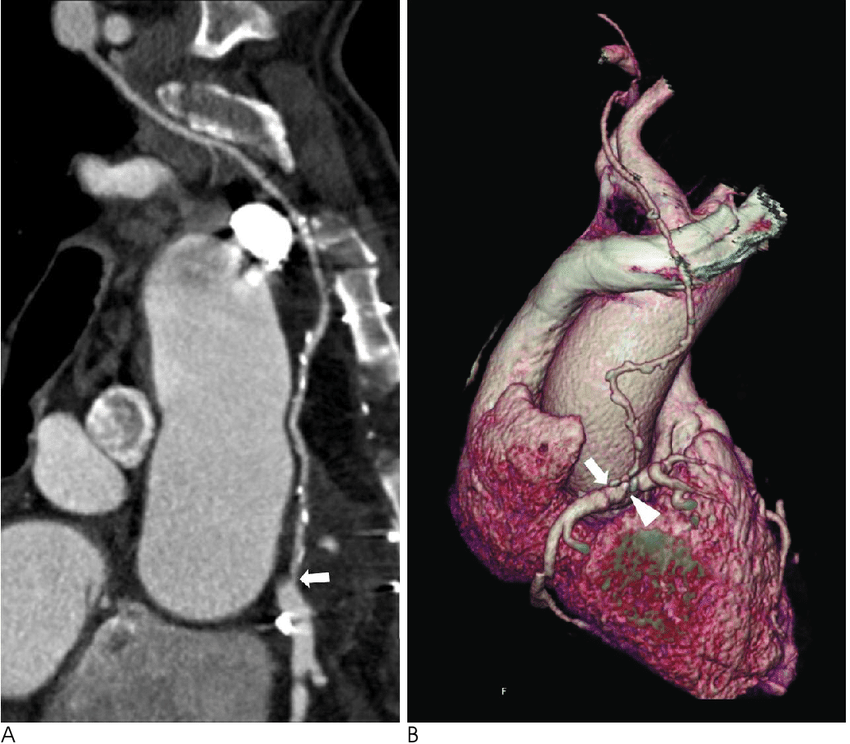

curved_mpr

( MPR ) Multi-Planar Reformat ve Curved MPR nedir ?

Multi-Planar Reformat (MPR) ve Curved MPR